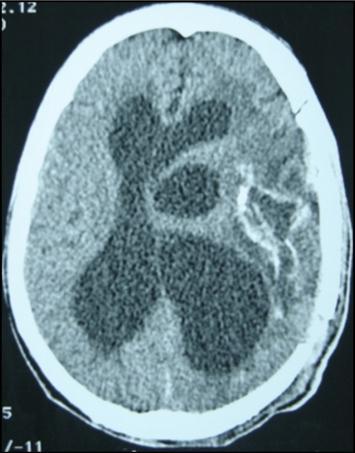

A 27 years-old male patient was admitted with 1 month history of headache, fever, short term memory lack, aphasia, right hemiparesis and seizures. He had liver hydatid cysts excised 8 years before and was treated with adjuvant medication (albendazole). The neurological examination revealed right central third cranial nerve palsy and hemi paresis, with Babinski sign positive, aphasia and papilledema on ocular fundus. The Glasgow Coma Scale was evaluated to 10/15 (E:3; V:1; M:6). A brain CT scan showed a large left temporoparietal intracerebral multiple and calcified hydatid cysts, important mass effect with midline shift about 7 mm following by an obstructive hydrocephalus (Figure 1). Other cysts were found in thalamic region (Figure 2). The Thoraco-abdominal CT scan showed multiple intra peritoneal hydatid cysts (Figure 3). A left temporo parietal craniotomy was performed in emergency. After corticectomy, using Arana-Iniguez technique, the appearance of the capsule suggested infected hydatid cysts with a purulent material which was aspirated. Numerous hydatid cysts were lifted away and several daughter vesicles were carefully removed without rupture (Figure 4). Macroscopically, the abscess wall appeared to be thick, calcified and tightly attached to lateral ventricular, so it could not be removed. The deep cyst overlying the third ventricle was left.in place. Microscopic examination demonstrated live scoleces, protoscoleces and multiple hooks. These findings are consistent with hydatid cyst (granulosis ecchinococcus) (Figure 5). Bacteriology examination found several white blood cells in the pus (neutrophilia) and infection by streptococcus pneumonia. This was consistent with infection. After surgery, the patient had medication (albendazole, specific antibiotherapy and phenobarbital). The inflammation assessment in the blood showed leukocytosis, a high C-reactive protein rate and increased erythrocyte sedimentation rate. Post operative CT scan was performed and showed the residual calcified capsule and decreased ventricular size (Figure 6). Clinical improvement was achieved after treatment. One month after the initial diagnosis, CT scan of the brain showed no recurrence and a physical examination revealed a neurologically intact, fully functional patient and eyes fundus normal. He was discharged and went to abdominal surgery two months later with complete intra abdominal cysts removal. Albendazole treatment was continuing for six months and radiological exploration was performed by brain MRI with spectroscopy at three and six month later. This showed that infection had resolved and the deep cyst overlying the third ventricle is less spherical (Figure 7, Figure 8). Four years later, the outcome was good.

Figure 1.axial CT scans of brain showing multiple hydatid cysts (A) with calcified capsule (B).